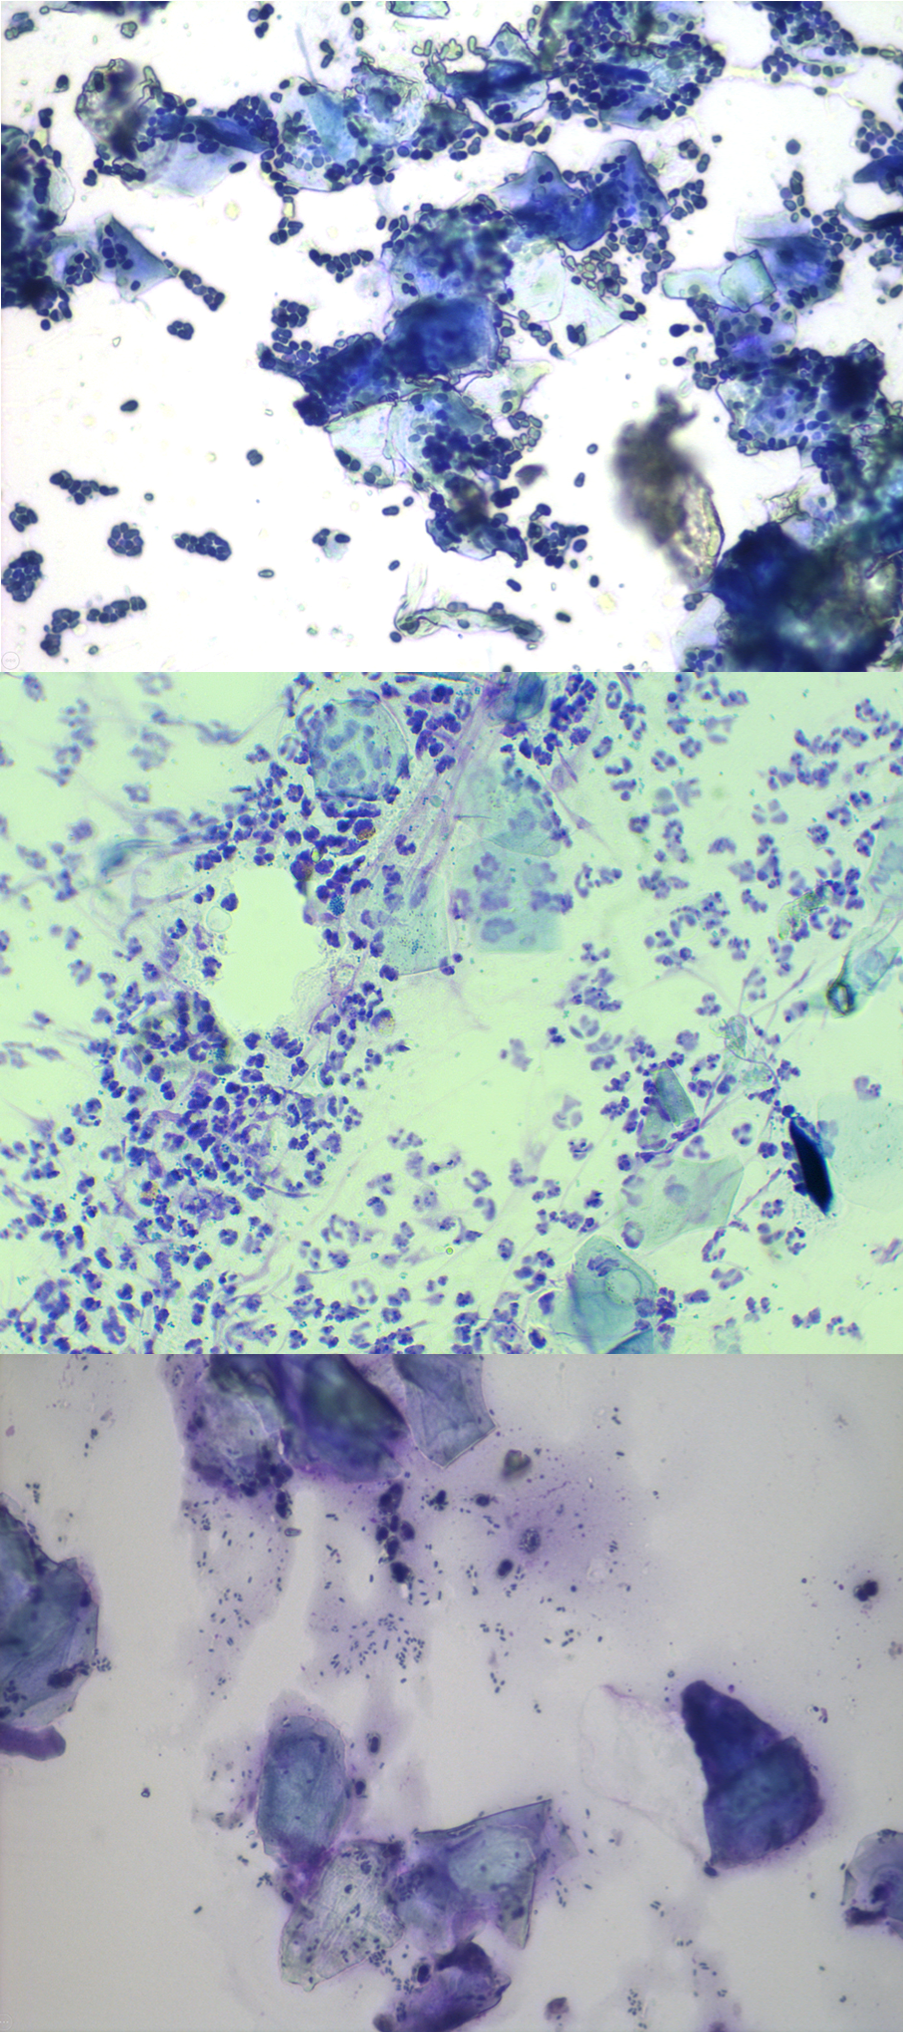

Disse bildene viser ulike stadier og former for ørebetennelse.

Bilder (CWalker, ThePhotoVet)

Det neste sterkt anbefalte trinnet i undersøkelsen er å ta en prøve av smuss fra hundens øre som skal studeres under et mikroskop, en prosess som kalles cytologi.

Cytologi er en rask og enkel test som kan utføres på veterinærklinikken. Den vil hjelpe veterinæren med å avgjøre om det er tegn på overvekst av bakterier eller sopp.

Ved hjelp av en cytologibørste, en bomullspinne eller muligens en finger med hansker, samles materialet opp fra hundens ører og plasseres på et objektglass. Prøven er farget med spesialfarge slik at veterinæren kan undersøke hva som foregår i hundens øre på mikroskopisk nivå. Alt for å avgjøre om det er overvekst av bakterier eller sopp og se etter inflammatoriske celler som ellers er usynlige for det menneskelige øyet.

Ikke bare gjør cytologien det mulig for veterinæren å velge en egnet behandling, men det er også nyttig å gjenta den ved kontrollbesøk for å evaluere om behandlingen av hunden har vært vellykket, eller om det er behov for endringer i behandlingsprotokollen, og for å bidra til å utvikle en langsiktig plan for hundens øreproblemer.